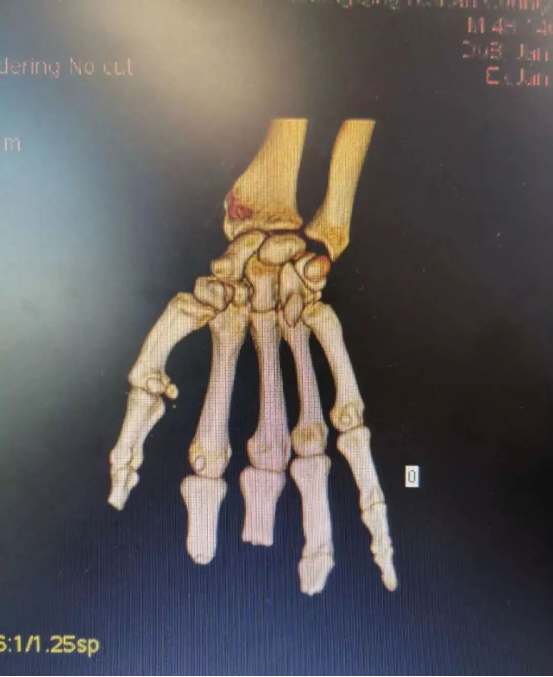

在放射科的支持下,醫院對患者雙手進行了CT三維重建,通過技術處理,虛擬出了患者缺失的手指,再使用新型材料打印出3D模型,模擬患者的斷指。通過對3D模型進行設計取樣,對患者右拇指、中指精準再造。